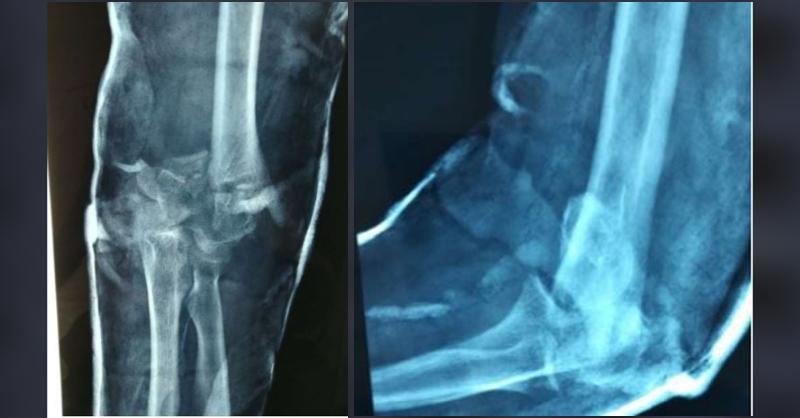

A 42-year-old female patient presented with painful, stiff elbow, and ulnar nerve neuropathy symptoms. On examination, the ROM (range of motion) of the right elbow was 60° of extension to 90° of flexion (total sagittal motion arc of 30°), along with a very compromised rotation of the forearm. This case was of malunited distal humerus fracture of th